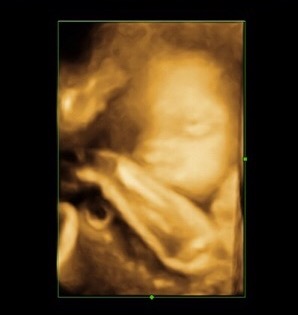

それも、室橋のカミさんが11月に女児を産むにあたり年末年始に動けない事を考え、両家の実家にお邪魔する考えです。

こんなにスクスク大きくなりました。